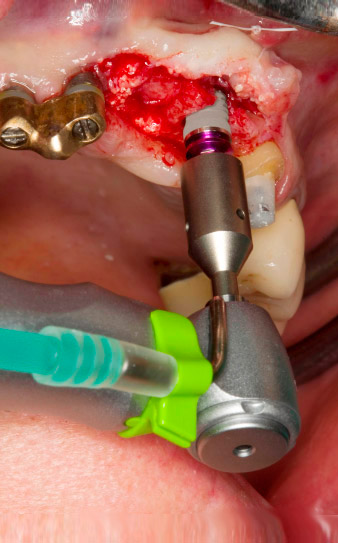

Motorized placement of the implant

Fig. 4: Motorized placement of the implant with the WS-75 L contra-angle handpiece at a ratio of 20:1 (programme P5).